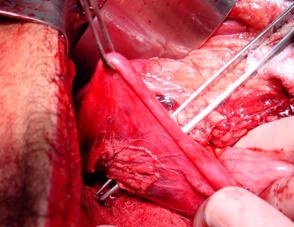

Traumatism

pelvian Hemipelviectomie dreapta posttraumatica

Ruptura de perete abdominal anterior